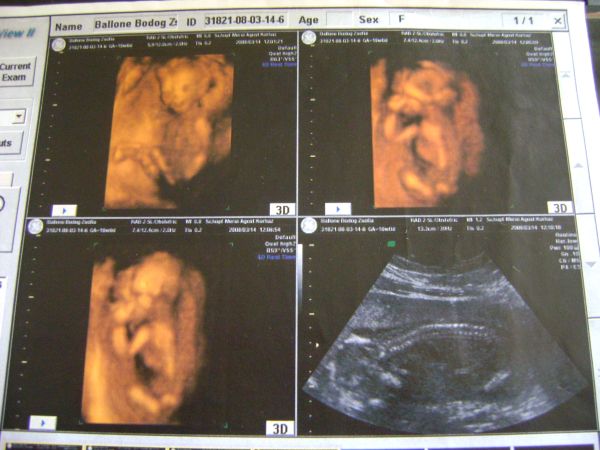

Rodina- Üdv köztünk, láttalak már az inszemes topikban, meg a blogodat is elolvastam mikor én is inszemeztem :D Iszonyú jó a fotó, remélem ma én is szert teszek egy ilyen gyönyörűségre :D

Angie34-Nagyon szép a fotóóóó :D Én is 4D-re a Praxis-ba tervezek menni,ha jól tudom ott van Hajdú Krisztina is, én is csak jókat hallottam róla!!! :wink:

Dorka- Gratula a babócádhoz, jó nagy már!!! :D Én is elszeretnék menni majd 4D-re ha megyek haza május közepén, elvileg 12-14-16 hét körül már tudnak valamit mondani, persze nagyban függ a géptől meg, hogy mennyire jó szonográfus az illető!!!Jó a sztárfotóó!! :D

Csajok ma megyek én is Uh-ra, Apjuk ha hazaér jön velem, olyan jó lesz újra látni!!! :D

hiper-szuper jó választás a 4D!

Én nagyon ajánlom mindenkinek!

Jövő pénteken megyünk, ííííí de várom! :D

24 és 28 hét között csodaszép élmény lesz az biztos!!! :D

Angie- Igen azért szeretnék oda menni, mertt ott van Hajdú Krisztina, meg Győrfi Mátyás, állítólag ő az egyik legjobb szonográfus, mondjuk azt nem tudom, hogy mitől függ, hogy kihez kerül az ember??Mivel csak 2-3 havonta jutok haza, így most elszeretnék menni, bár tudom, hogy kép ügyileg még nem lesz egy nagy durranás, de hátha a nemét már megmondják....Aztán legközelebb júliusban megyünk, akkor már Apjukkal, gondolom, hogy akkor már sokkal szebb képeket lehet csinálni a babóról, olyat amin nem úgy néz ki, mint egy kis Alien :D :D :D Itt kint megmondom őszintén ( Ausztria) nem nagyon nézegettem kocsikat, csak neten, de azok közül baromira nem tetszett egyik sem....Viszont nyílt nem messze egy 800nm-es bababolt, oda azért lehet majd bekukkantok, hogy mit adnak mennyiért :D Mindenképpen jövök a hírekkel Uh után :wink:

ja, és első babás anyukák figyelmébe ajánlom... nekem van elég sok 4D felvételem Beniről, ha gondoljátok befotózom, hogy lássátok, melyik héten milyen, persze csak, ha érdekel valakit! de amúgy a nemét általában a 18. heti genetikai uh-n már meg tudják mondani, az már mellékes, hogy nálunk ez olyan 23. hét környékére tolódott 100%-ra, mert addig csak fiú gyanús volt... :) szóval nagy mázli kell hozzá, hogy a 12. hetinél kimutassák, hogy mizu! :S